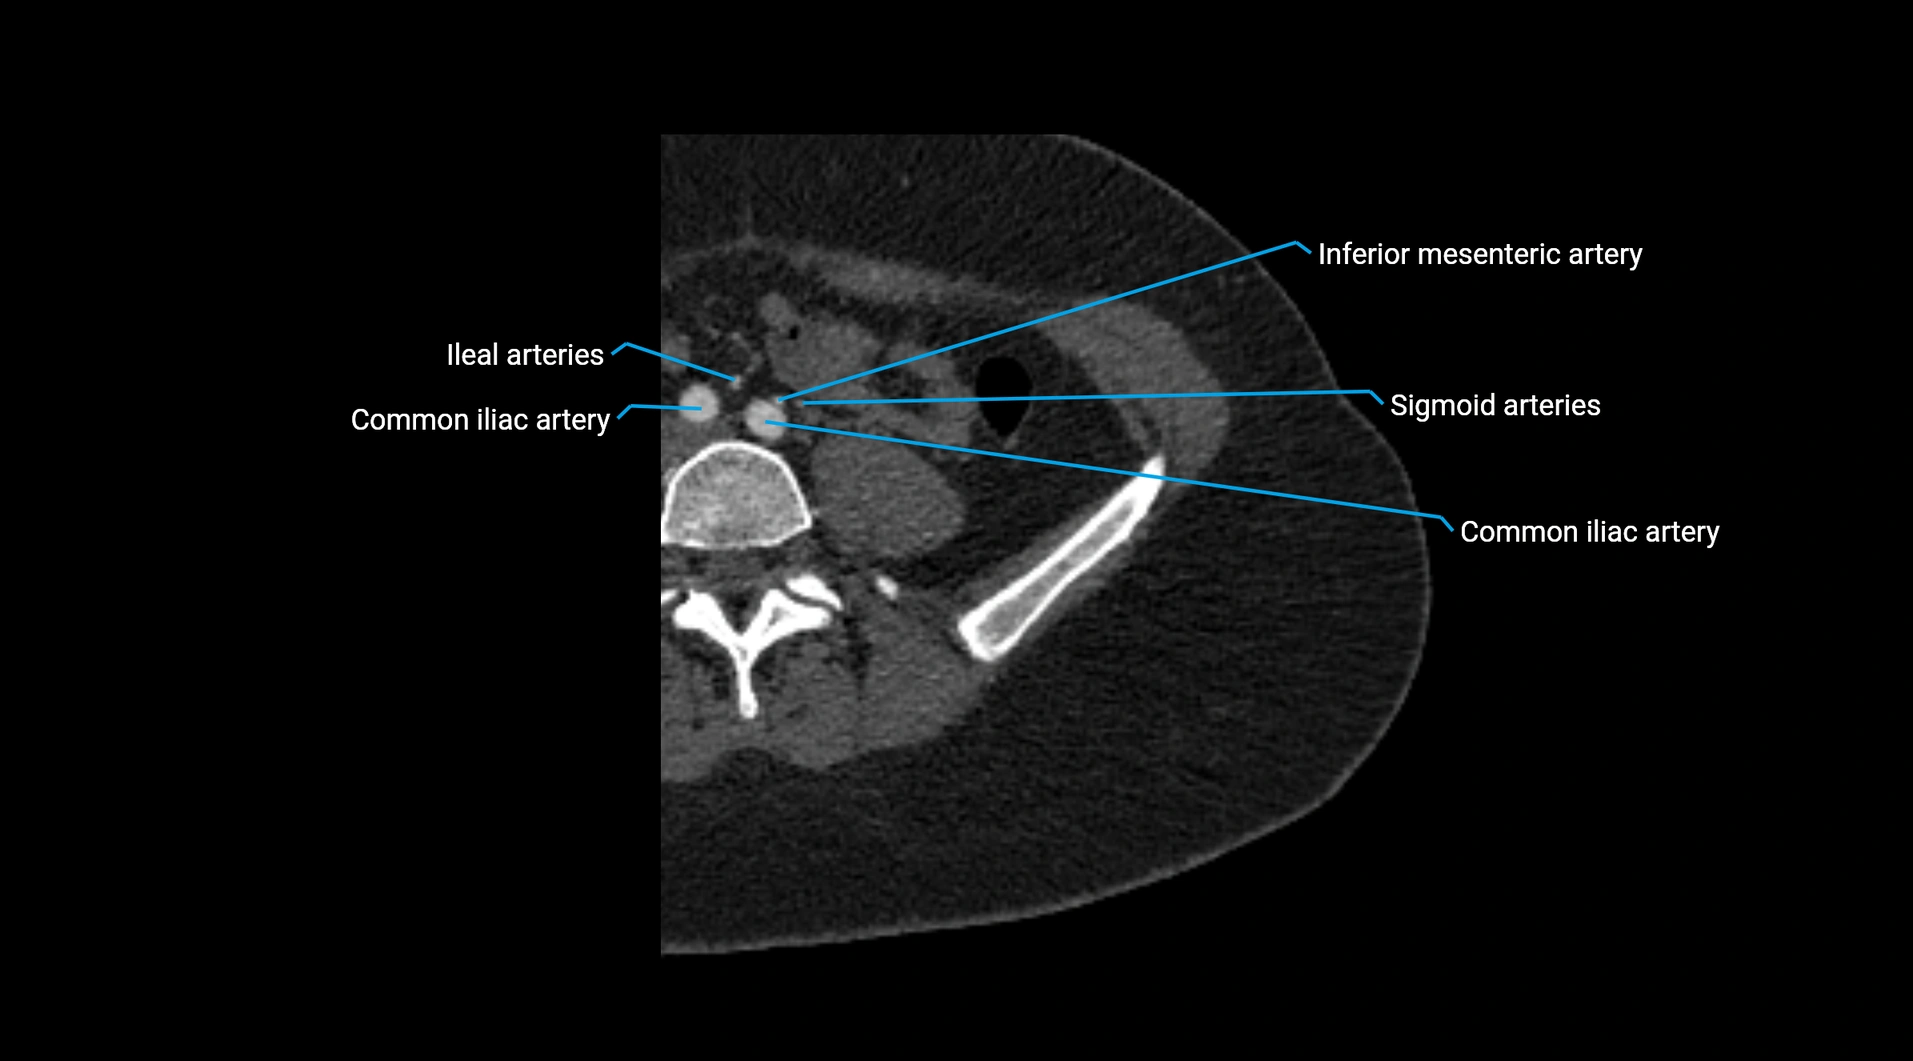

Contrast-enhanced CT (CTA):

• Gold standard for abdominal aortic imaging

• Provides excellent detail of lumen, wall, aneurysm, thrombus, and branch vessels

• Multiplanar and 3D reconstructions help in aneurysm measurement, stent graft planning, and dissection evaluation

• Detects acute rupture, traumatic injury, or occlusion with high sensitivity